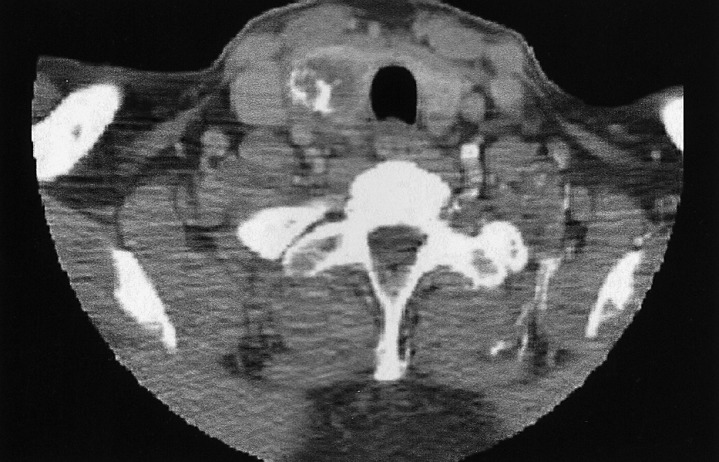

A physical examination revealed a hard, non-tender mass with a maximum transverse diameter of 3 cm on the right side of the thyroid gland. Palpable lymphadenopathy was absent in the cervical and supraclavicular area, and a laryngoscopic examination showed no abnormal findings from the oral cavity to the larynx. Laboratory examination showed a serum TSH level of 3.22 mU/L (reference range 0.30~5.00), T3 1.66 nmol/L (0.92~2.78), T4 78 nmol/L (58~140), anti-thyroglobulin antibody 1 U/mL (0~100), anti-microsomal antibody 1 U/mL (0~100), and thyroglobulin 170.1 ng/mL (0~25). There were no abnormal findings on the hematologic and biochemical laboratory tests. Neck computed tomography (CT) showed a low attenuated, calcified mass with a maximum diameter of 3 cm on the right side of the thyroid gland (Figure 1). An ultrasonography-guided fine needle aspiration and cytology (FNAC) showed a small number of benign follicular cells without atypical cells. Chest X-ray and CT showed a 1 cm sized nodule in the upper lingular segment of the left lung; this nodule was previously diagnosed as a carcinoid, and was noted to have decreased in size. However, three small nodules were newly detected in the left lower lobe of the lung by comparison with prior films (Figure 2). The new nodules noted in the left lower lobe of the lung were diagnosed as follicular neoplasm by FNAC.

Neck CT showing a low attenuated, calcified mass with a maximum diameter of 3 cm in the right lobe of the thyroid gland.